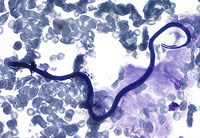

Giun chỉ Loa Loa có kích thước con đực dài từ 25-35 mm, to khoảng 0,30 mm ; con cái dài từ 50-70 mm, to khoảng 0,5 mm. Ấu trùn giun dài từ 250-300 µm, to khoảng 6-8 µl.